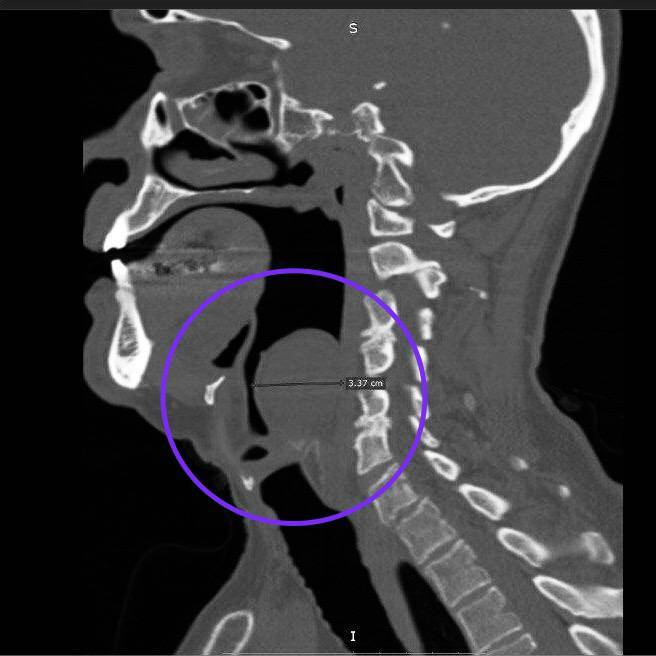

Гигантскую доброкачественную опухоль – миксому удалили оториноларингологи Республиканской клинической больницы из гортани пациента. Об этом рассказали в пресс-службе клиники.

Уникальность случая в том, что обычно миксомы вырастают в сердце. Подобное образование в горле – редкость. В России было описано всего два подобных случая.

Однако у 67-летнего татарстанца опухоль из соединительных тканей выросла уже во второй раз.

«Впервые образование выросло до трех сантиметров в диаметре еще в 2021 году. В лор-отделении РКБ Татарстана его прооперировали и благополучно вписали. Но весной этого года мужчина снова пошел к врачам – вновь выросшая опухоль мешала ему глотать пищу», – объяснили в пресс-службе РКБ.

На этот раз оториноларингологи больницы удалили образование диаметром уже восемь сантиметров. Операция длилась полтора часа. Удалили опухоль через рот, дополнительные разрезы не потребовались. Сейчас мужчина идет на поправку.